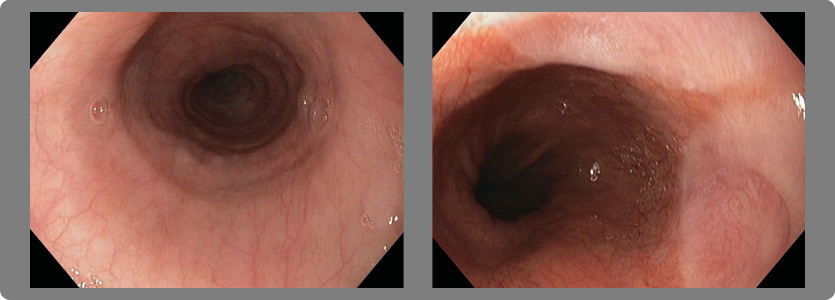

1- Esofagitis

Existen 4 grados diferentes de acuerdo a la severidad de las lesiones.

- Grado A:

Una o más úlceras no mayores de 5 milímetros que no se extiendan entre las crestas de los pliegues mucosos.

- Grado B:

Una o más úlceras mayores de 5 milímetros que no se extiendan entre las crestas de los pliegues mucosos.

- Grado C:

Úlceras que se extienden entre las crestas de uno o más pliegues mucosos pero que afecta a menos del 75% de la circunferencia

del esófago.

- Grado D:

Úlceras de la mucosa que afectan al menos 75% de la circunferencia del esófago.